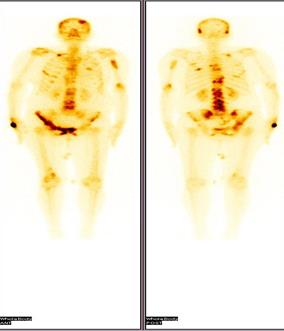

It is easy to use, widely available and less expensive. Moreover it does not use any ionizing radiation, gives a clearer picture of soft tissue that cannot be seen in X-rays, causes no health problems and can be repeated as much as can if indicated for any health problems. It provides real-time-imaging so Is perfectly good for minimally invasive procedures such as needle biopsy and fluid aspiration. The disadvantages if the transrectal USG is that the patients with their bowel removed during or prior surgery are not good candidates for USG of the prostate as it always require a placing a probe into the rectum.

When prostate cancer is suspected, the diagnostic test of choice is a systematic needle biopsy with US guidance. Before biopsy, the patient is prepped with an enema and antibiotics (quinolone analogs). With the patient in the decubitus position, the transrectal US probe is placed in the rectum, the prostate and seminal vesicles are visualized, and the images are recorded in transverse and sagittal planes. And moreover the biopsy can be taken simultaneously under the USG guidance. A single biopsy session has a sensitivity of 70%–80% for the detection of cancer. To minimize the need for repeat biopsy sessions, many physicians obtain more cores the first time. Separate samples of the anterior prostate (or transition zone) are usually not obtained unless previous biopsy sessions have failed to find a suspected cancer (eg, in a patient with a high PSA level, abnormal findings at digital rectal examination [DRE], and multiple negative peripheral zone biopsy specimens), or imaging with transrectal US or MR suggests an anterior cancer [[103]].

Diagnostically, transrectal US is used to measure the volume of the prostate gland, an important factor in computing “PSA density” (serum PSA level in nanograms per millilitre divided by the volume of the prostate in cubic centimetres). Moreover, the volume as measured with transrectal US can be used in staging and in predictive nomograms. Cancer, depending on its size, grade, and location, usually appears hypoechoic relative to the normal peripheral zone of the prostate (only approximately 1% are hyperechoic). As a diagnostic test for cancer, transrectal US without biopsy is as accurate as DRE and complements the physical examination. Some palpable cancers are not visible at US, and some visible cancers are not palpable. With the shift toward smaller, early-stage cancers, many cancers detected at biopsy are not visible at US (low sensitivity) and many hypoechoic areas do not prove to be malignant at biopsy (low specificity); therefore, transrectal US alone, without the addition of biopsy, has limited value in the detection of cancer [[104]].

Transrectal ultrasound has been used for the staging of primary cancer but is generally considered insufficient. The criterion for identifying extracapsular extension on transrectal US scans are bulging or irregularity of the capsule adjacent to a hypoechoic lesion. The length of the contact of a visible lesion with the capsule is associated with the probability of extracapsular extension. Seminal vesicle invasion (SVI) is heralded by a visible extension of a hypoechoic lesion at the base of the prostate into a seminal vesicle or by echogenic cancer within the normally fluid-filled seminal vesicle. Asymmetry of the seminal vesicles or solid hypoechoic masses within the seminal vesicles are indirect indicators of disease extension. When extraprostatic extension into the seminal vesicles is suspected, additional transrectal US-guided biopsies of the seminal vesicles can be performed.